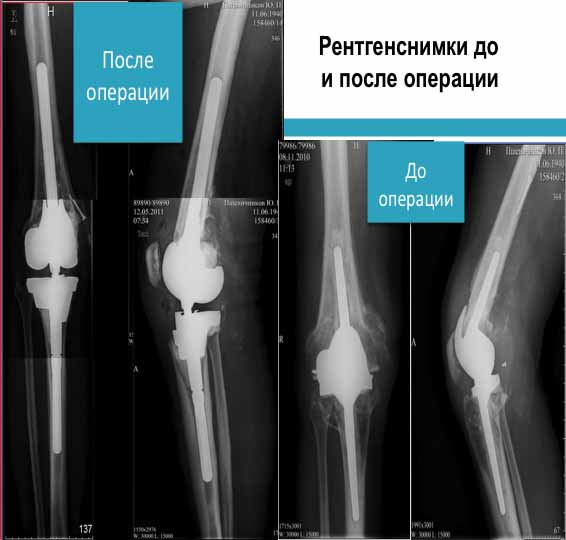

У нас есть опыт протезирования пациента с массивными костными дефектами бедренной и тибиальной кости. С помощью данных аугментов обошлись без аллокости.